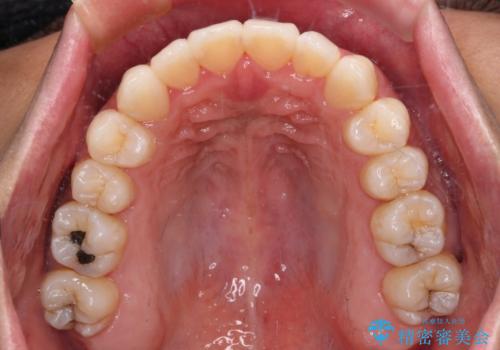

- 全体的なデコボコと、前歯の前に出ている感じを気にして来院された患者様です。

患者様と相談の上、非抜歯にてインビザラインを用いて矯正治療を行うこととし、IPR(歯と歯の間)並びに歯列全体の後方移動により口元の突出感の改善することとしました。

お仕事が忙しい方で、装着時間が不足したり、定期的な通院ができなかったりと、自己管理が重要なインビザラインによる矯正治療が長期化する要因が重なり、5年ほどの期間を要しました。